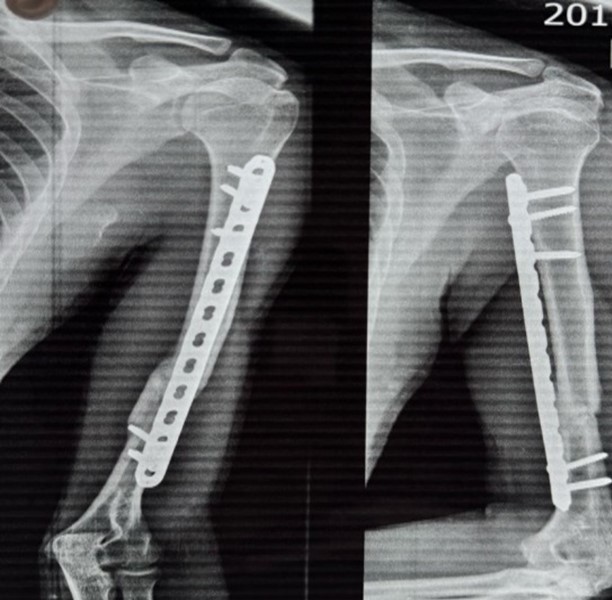

35 year old male patient suffering from closed displaced diaphyseal humerus fracture without distal neurovascular deficit. Follow up was taken at 3months post operatively and 12 months post operatively

12 month follow up

The patients shoulder and elbow function were analyzed using the UCLA shoulder score18 and the Mayo elbow performance score (MEPS)19 The UCLA shoulder score was graded into excellent to good (>27 points), fair to poor (<27 points). Elbow function was graded on the MEPS basis into excellent (≥90 points), good (75–89 points), fair (60–74 points), or poor (<60 points). Based on the anteroposterior and lateral radiographic view Union was accepted as the presence of bridging callus in three of the four cortices and absence of pain. Also any loss of fracture reduction was analyzed in similar radiographs.